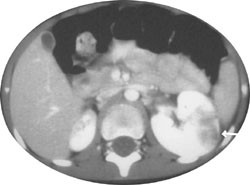

Pasient 2. 19 måneder gammel gutt som ble henvist sykehuset på grunn av høy feber og lysskyhet, med mistanke om alvorlig infeksjon. Ved sykehuset ble det målt CRP på 105 mg/l. Ved undersøkelsen var han i god allmenntilstand, og reiste derfor hjem med avtale om kontroll av blodprøver påfølgende dag.

Ved neste konsultasjon var CRP 310 mg/l og pasienten var høyfebril. Abdomen var bløt og uøm, uten bankeømhet over nyrelosjer. Urinstiks var negativ. Mikroskopisk undersøkelse av urinen var gjentatte ganger normal. Ingen vekst av bakterier i blodkultur. Til tross for usikker infeksjonsfokus ble det gitt antibiotika intravenøst i form av cefotaksim. I den videre utredningen ble det gjort CT-undersøkelse av abdomen, som viste fokale forandringer i venstre nyre og en liten, skrumpet høyre nyre (fig 2).

Antibiotikumet ble skiftet til mecillinam da man fikk svar på oppvekst av enterokokker i urin tatt ved innkomst. Miksjonsureterocystografi viste ved kontroll etter seks uker bilateral vesikoureteralrefluks grad 1. Diureserenografi viste en funksjonsfordeling på 89 % venstre nyre, 11 % høyre nyre. Pasienten følges ved lokal poliklinikk med årlige kontroller og har siden ikke hatt urinveisinfeksjoner.